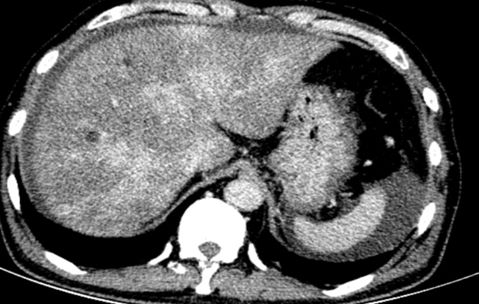

进一步检查及确诊:增强CT检查:下腔静脉肝段狭窄,内可见造影剂填充,肝脏异常强化(肝脏弥漫密度减低,门脉静脉期及平衡期显示肝脏不均匀强化,肝静脉周围呈片状明显强化,余肝实质呈轻度强化);腹部MRI:肝实质信号不均、肝静脉显示不清、腹水;肝脏病理活检:肝小叶结构未见异常,小叶中央为主的肝细胞片状退变坏死,灶性区域可见肝窦内淤血现象,形态提示缺血或淤血改变,致病因素包括药物/毒物、流出道梗阻(VOD、布加综合征)。免疫组化结果:CD34染色未见异常,CK7染色显示局部胆小管增生,局部肝细胞胆管化,HBsAg(-),特殊染色结果:Masson染色显示汇管区纤维组织增生,PAS、PAS+消化、铁、铜染色未见异常,网织纤维局部破坏。追问病史,患者起病前2月曾服用“三七粉”1月。最终诊断为吡咯生物碱相关性肝窦阻塞综合征。

CT: